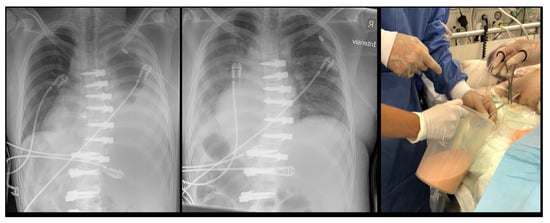

| 3 | 16.2 | F | 4 | T5-T12 right | Contralateral atelectasis | 2 days | Left | Severe dyspnea | Re-intubation for 3 days, 3 bronchoscopies and removal of a mucus plug |

| 11 | 12 | F | 4 | T5-T11 right | Haematothorax | 1 day | Right | No symptoms, significant blood loss noticed after declamping the chest tube and drop of haemoglobin levels | Emergency explorative thoracotomy using the same surgical approach. No active bleeding found but clotted hematoma |

| 12 | 13 | F | 2 | T6-T12 right T12-L4 left | Haematothorax | 6 weeks | Right | Acute chest pain | Emergency explorative thoracotomy |